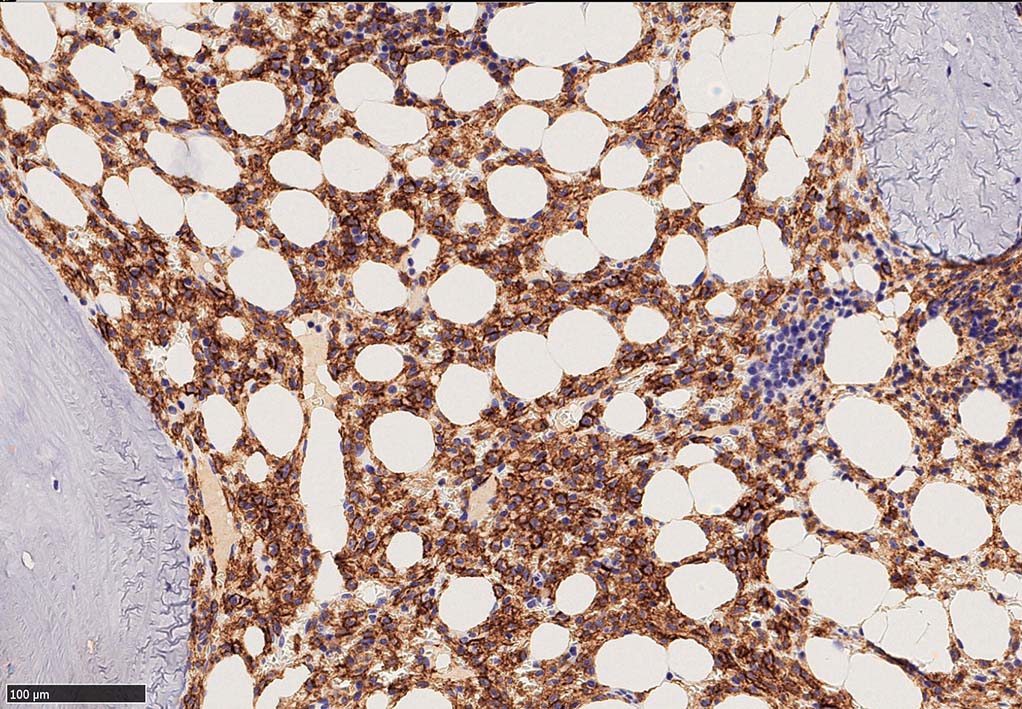

増殖細胞はCD20(相変わらずべったり染まる), CD19, PAX5陽性 CD25陽性.

BRAF V600E変異タンパクの免疫染色(山梨医大 大石先生に染色していただきました. ベンタナ, Optiview)

Pathological Diagnosis: Hariy cell leukaemia